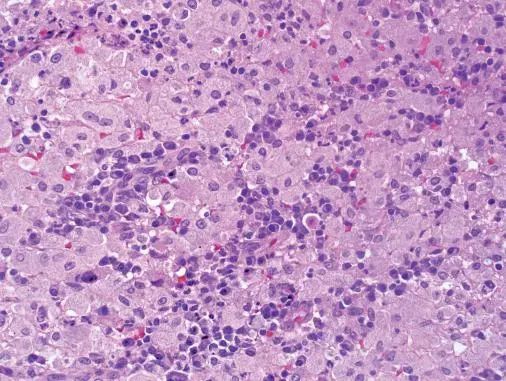

1[单选题]如图为肾结核结节镜下观,箭头所指细胞称之为

干酪样坏死-淋巴结结核